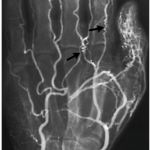

ANGIOGRAM (X-RAY)

The following gallery shows examples of Buerger disease seen on X-ray angiograms. Click the thumbnails below to open up the gallery.